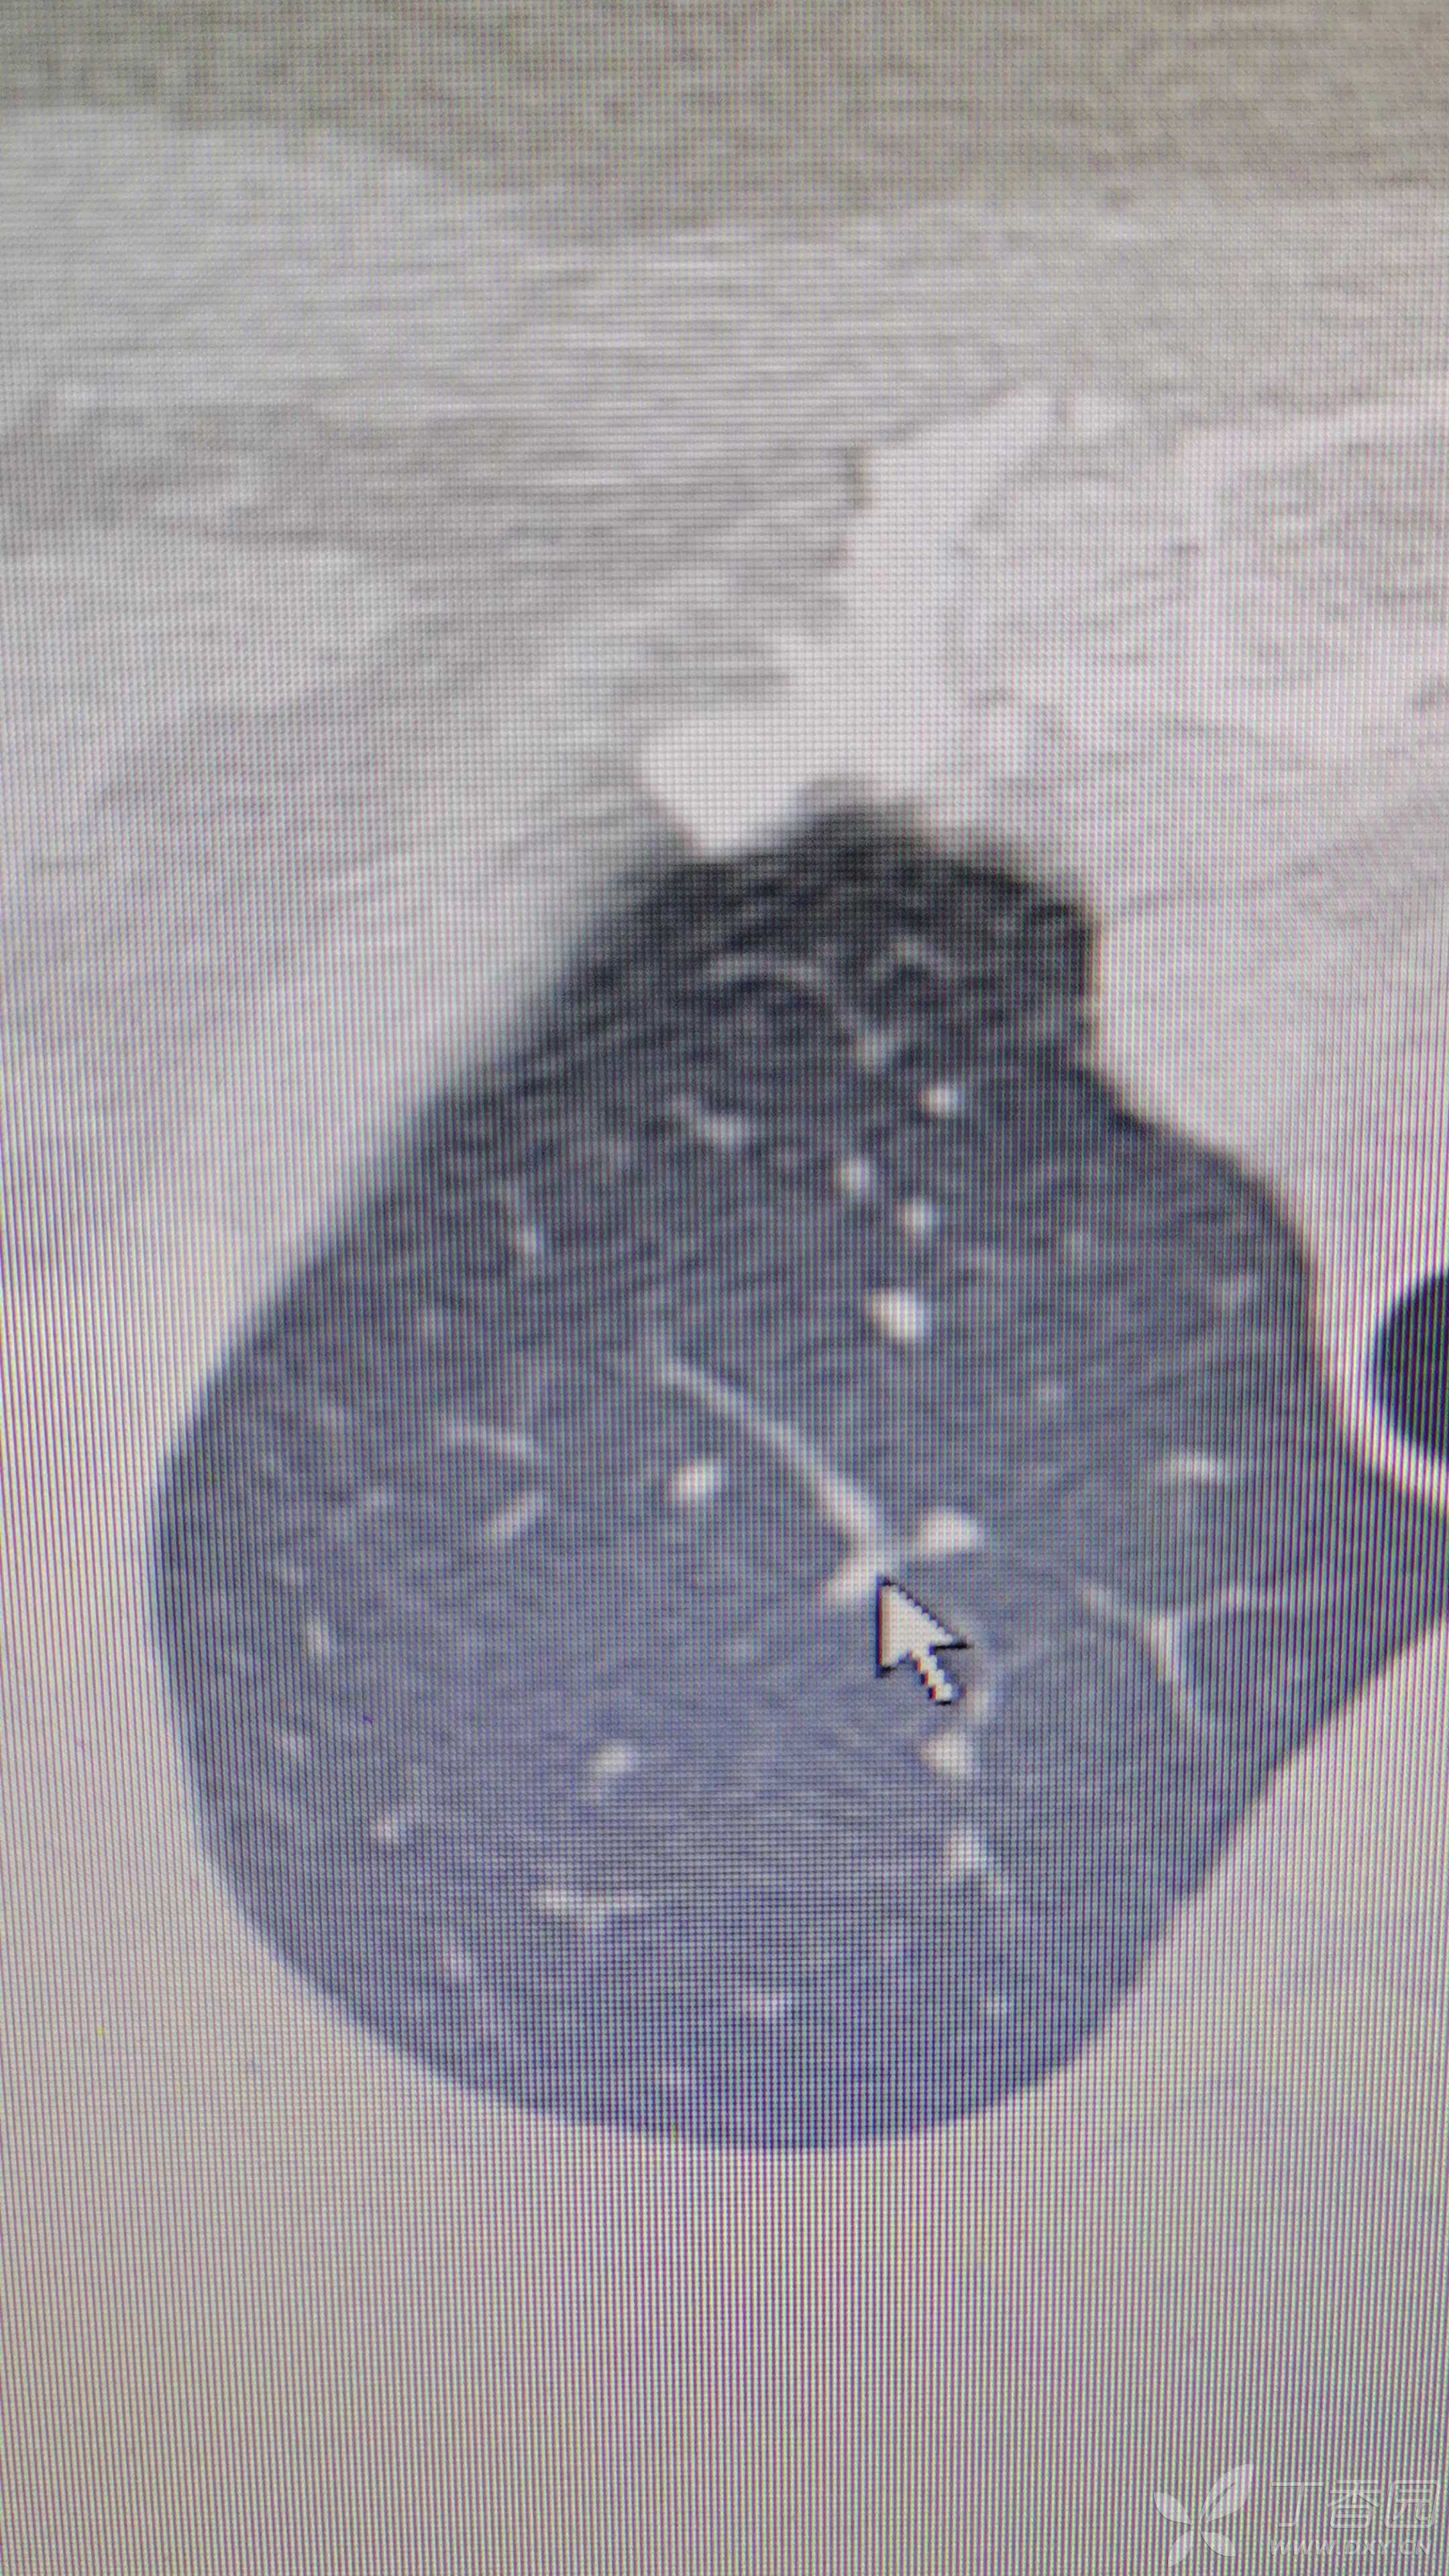

复查胸部ct

病史:患者女,59岁,自诉半年前受凉后反复咳嗽咳痰,期间头孢输液三天后症状好转,其后偶有咳嗽,无畏寒发热,咯血胸闷,夜间盗汗。2021-11-29查胸部ct:右肺上叶多发异常密度影,考虑感染。怀疑结核可能,入院后查血常规正常。痰检三次阴性,支气管灌洗液涂片阴性,培养阴性。支气管镜检查见左侧支气管及各侧支气管均有较多痰栓附着,较难吸出。结核T-SPOT阳性。予以美洛西林+乳酸左氧氟沙星抗感染治疗10天,复查胸部ct病灶未见明显吸收。胸部ct2021-12-10示:右肺上叶及中叶多发高密度影。